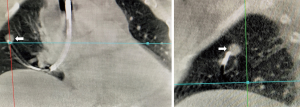

The miniaturization of the radial probe has allowed for imaging of peripheral lesions beyond the segmental airways. In this capacity, the ultrasound probe, albeit typically without a balloon, can be placed through the working channel of the bronchoscope and extended into the periphery to identify intrapulmonary nodules (6). Utilization of this technique has evolved in several ways. The radial probe can be extended through the bronchoscope to identify the lesion, leaving the bronchoscope in the appropriate subsegment and replacing the probe with biopsy tools. The addition of a guide sheath may improve diagnostic yield (7). The radial probe can be directed to the nodule via a sheath catheter and after the probe has been removed biopsy of the nodule can be done with or without fluoroscopy through the catheter that has been directed to the nodule. Using the latter technique, diagnostic yield for peripheral pulmonary nodules 2–3 cm can be as high as 72%, at single centers versus yields as low as 20% for bronchoscopy alone (7,8). If a concentric view is obtained, where the nodule encircles the probe, the diagnostic yield improves to 84% and has similar, if not improved yield, compared to computed tomography (CT) guided biopsy, with fewer complications (Figure 1) (7,9). When RP-EBUS has been combined with electromagnetic navigational bronchoscopy (ENB) the diagnostic yield for peripheral nodules is increased versus either technique alone (10,11). TBNA of the peripheral pulmonary nodule can also improve diagnostic yield by nearly 10% versus brush biopsy or forceps biopsy (12).

There are many novel ways EBUS is being used in the diagnosis and treatment of intrathoracic disease. We and others have combined RP- EBUS and CP-EBUS with cone beam CT to facilitate biopsy of difficult to locate central and peripheral pulmonary nodules (Figures 3,4) (65). A randomized controlled trial is currently underway to determine if this technique improves diagnostic yield (NCT02978170). For thyroid malignancy EBUS has been used for diagnosis and staging in patients with lesions not amenable to percutaneous biopsy (66). It has also been used to evaluate for airway invasion in the setting of esophageal and thyroid cancer and has higher sensitivity and specificity than magnetic resonance imaging or CT (67). EBUS may also play a role in diagnosis and treatment of cardiac disease and has been used to facilitate percardiocentesis for posterior loculated pericardial effusions (68). Among 32 patients with CT proven pulmonary embolism, EBUS was utilized in a pilot study to confirm a diagnosis of central pulmonary embolism in every patient with an average procedure time of only five minutes (69). EBUS has been utilized for bronchogenic cyst drainage in patients who were not good surgical candidates and for treatment of cyst recurrence after partial resection (70,71).